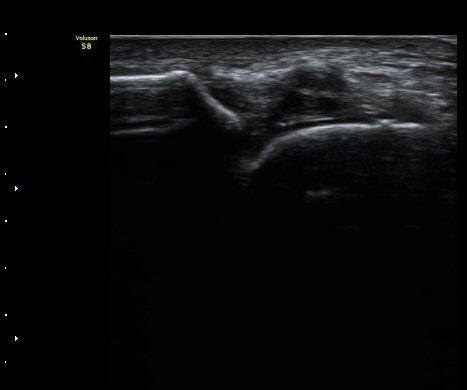

Àü°Å°ñºñ°ñÀδë Á¾´Ü¸é°Ë»ç¿¡¼­ ÀδëÀÇ ÀüÃþÆÄ¿­°ú ºÎÁ¾ÀÌ °üÂûµÈ´Ù(±×¸² 3, 4).

°ÇÃø(±×¸² 5)°ú ºñ±³ÇØ º¸¸é È¯ÃøÀÇ ÀÎ´ë ¼Õ»óÀÌ ¶Ñ·ÈÇÏ´Ù.